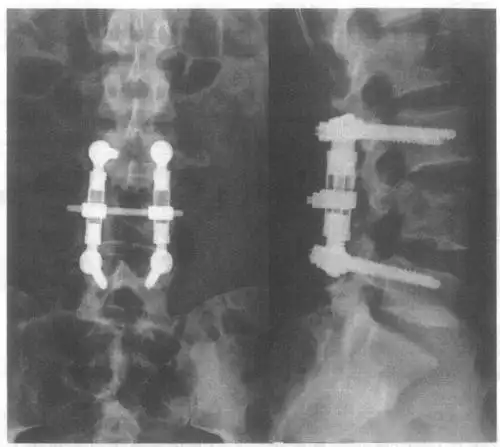

图20-1 l  椎体压缩性骨折行椎管减压复位af固定术后